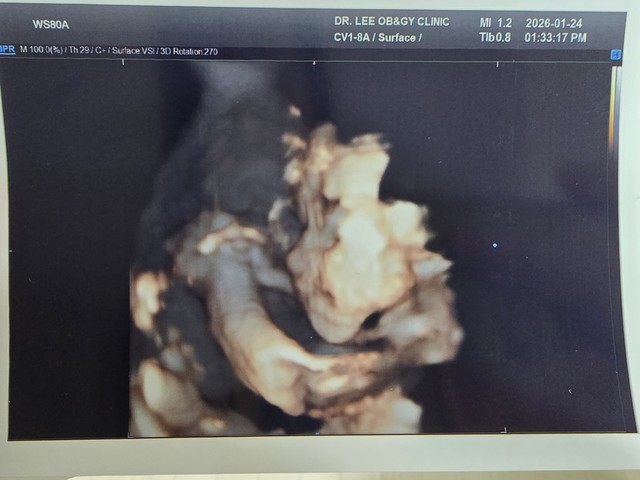

오랜만에 셋째 소식

26.01.25

오랜만에 뱃속에 있는 셋째 소식이에요.어느덧 임신 7개월째네요.노산이라.. 검사도 따로 했고 기형아 검사도 무사히 통과했어요.초기에 입덧으로 고생을 좀 했지만 지금은 잘 먹고 있어요.어제 임당 검사, 빈혈 검사, 독감 접종까지 했네요.어제 안 사실인데 탯줄 한바퀴가 목에 감겨 있다고!!!1호, 2호는 그런 적이 없는데 식겁했네요.병원에서 선생님께서 괜찮다고 하셨으니 믿으려구요.804g으로 잘 자라고 있다고 합니다.